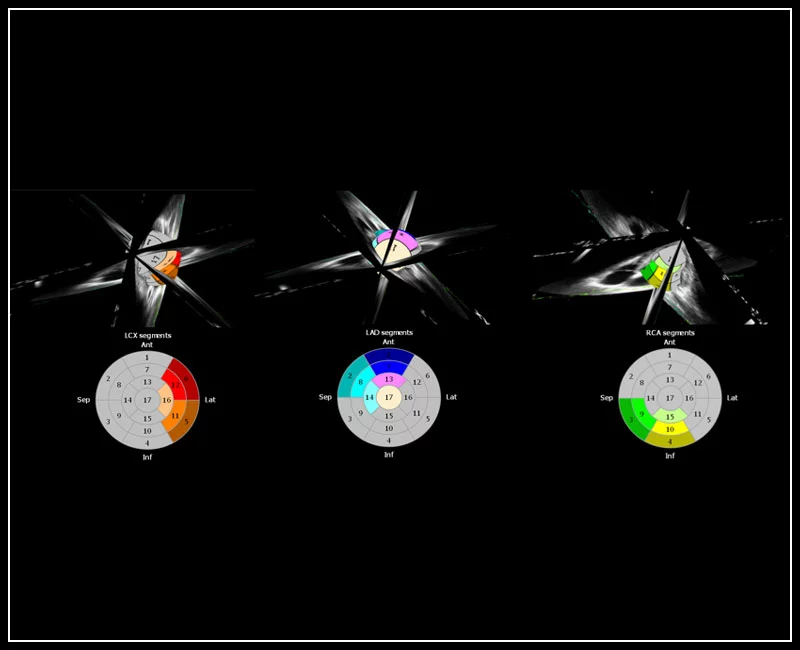

MyLab™9 Platform - XStrain4D technology for volumetric heart assessment by coronary territories

MyLab™9 Platform - XStrain4D technology for volumetric heart assessment by coronary territories